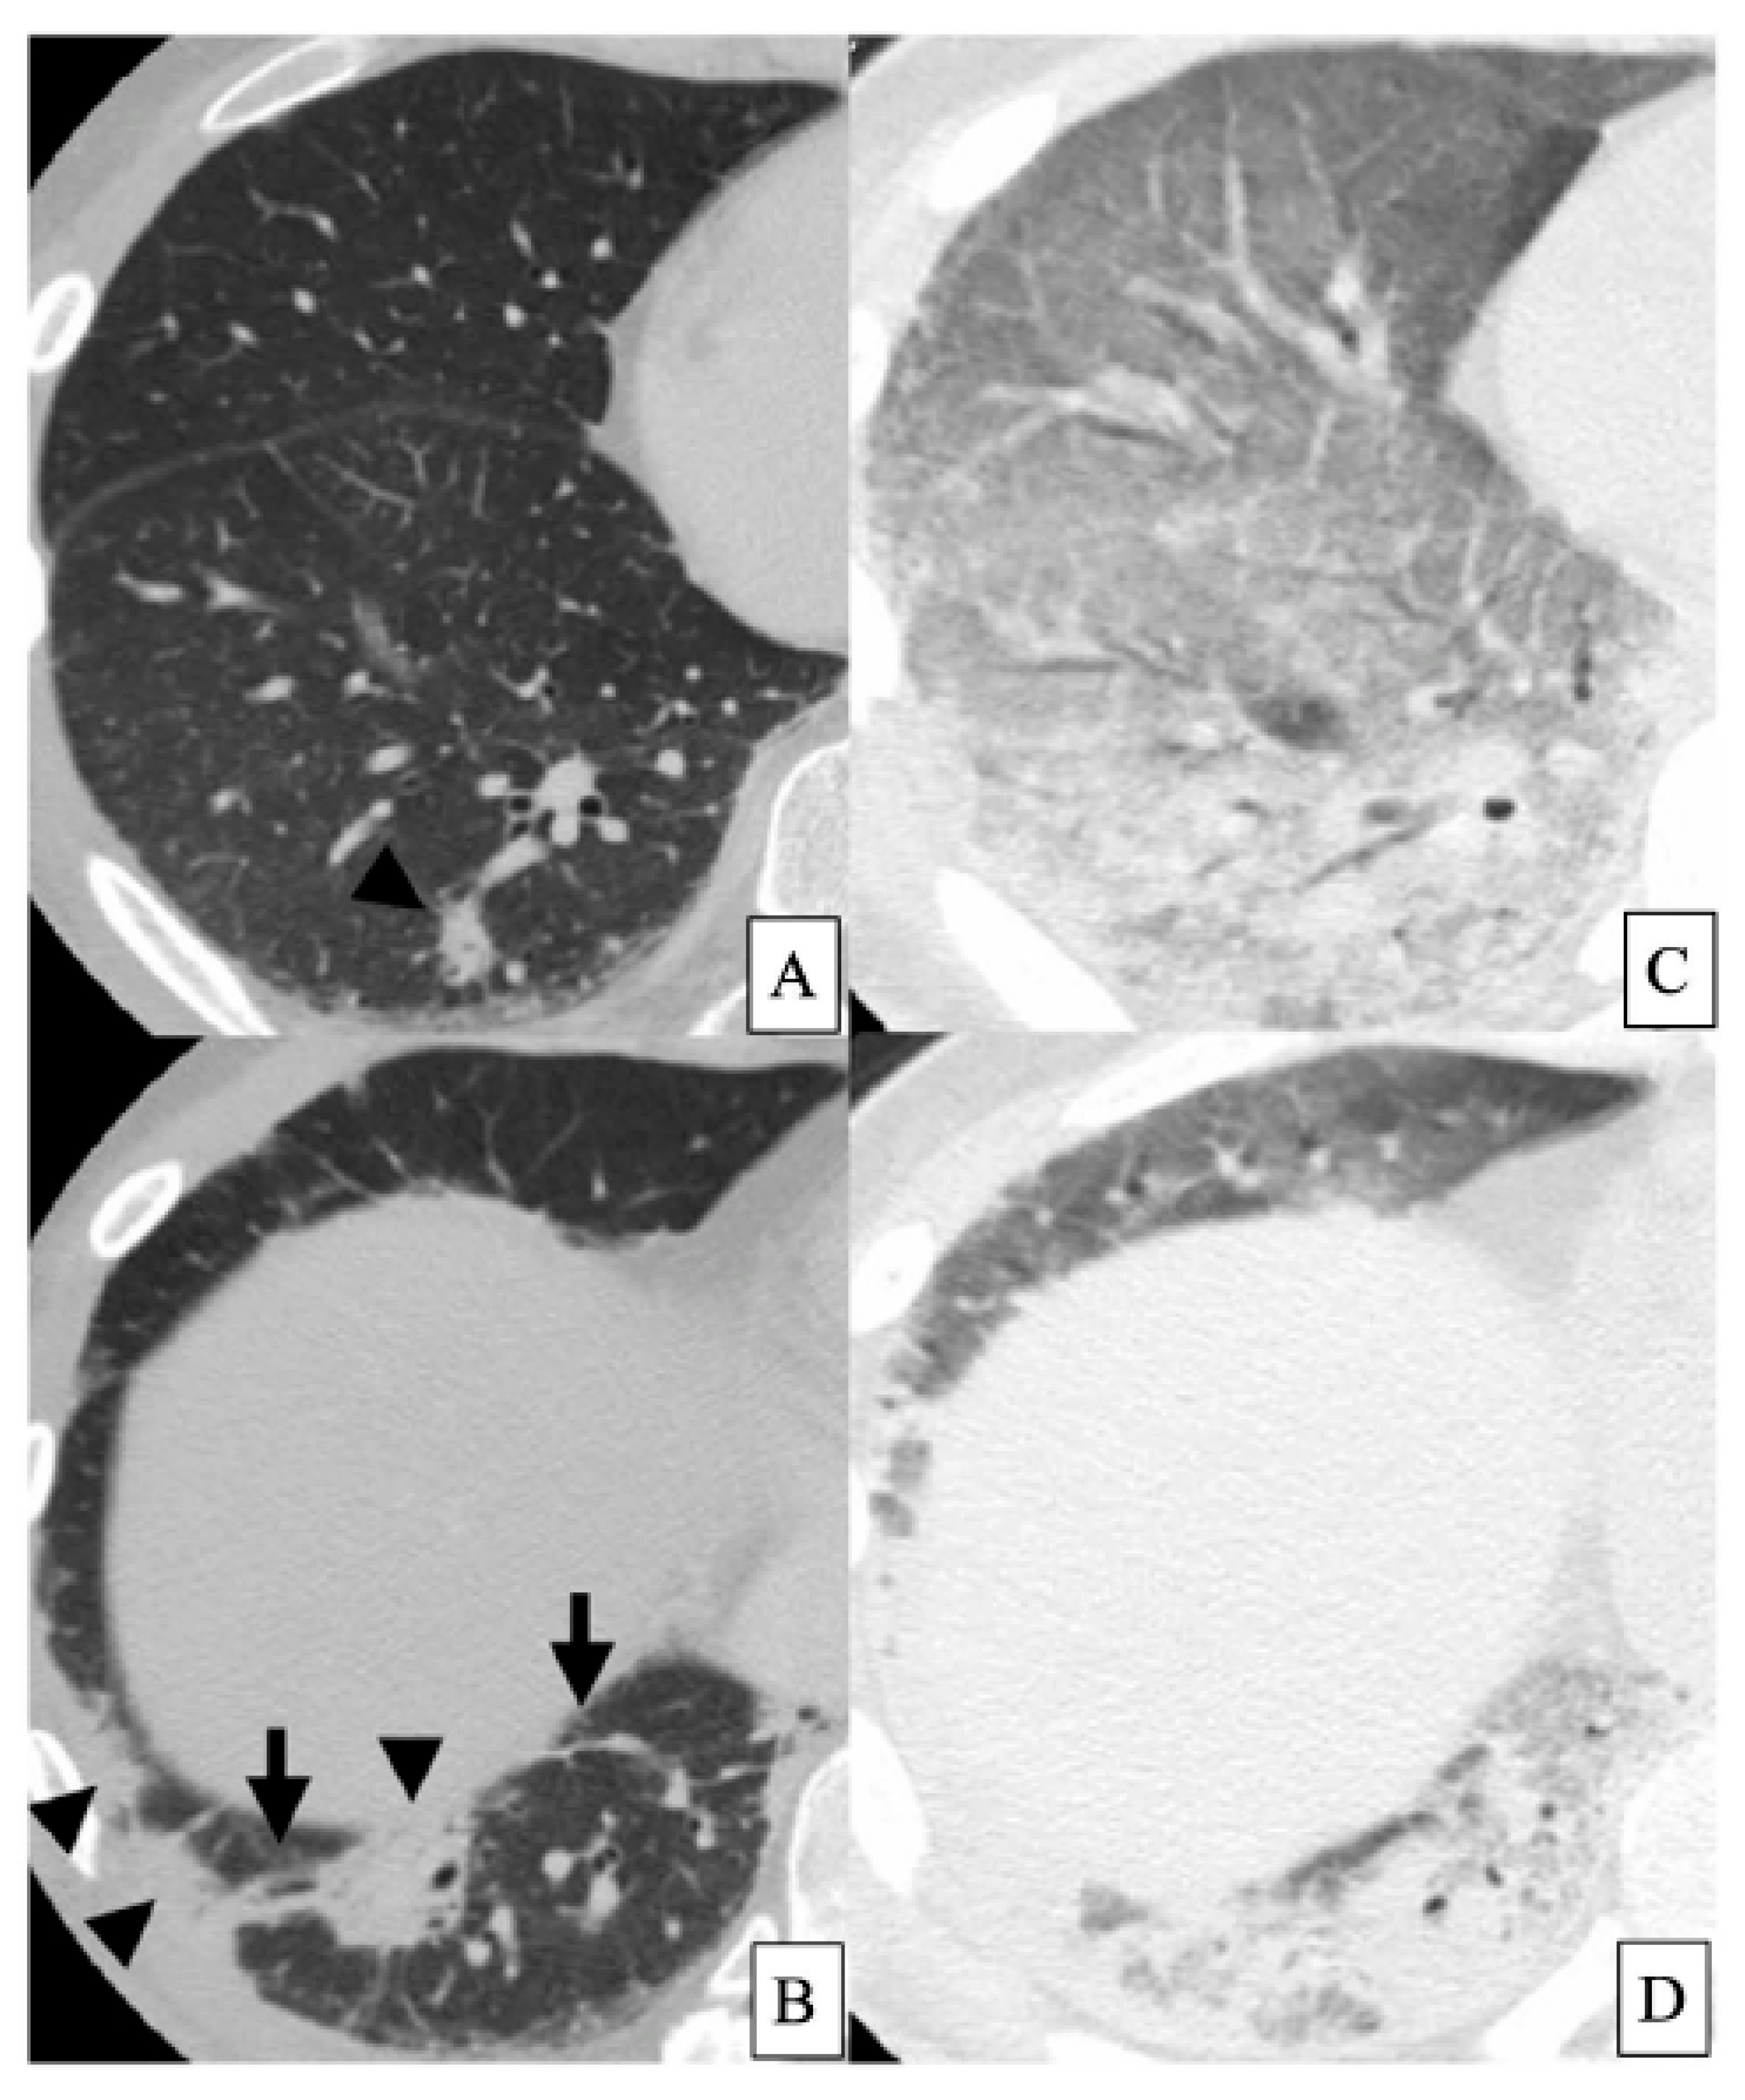

- Akira, M.; Hamada, H.; Sakatani, M.; Kobayashi, C.; Nishioka, M.; Yamamoto, S. CT findings during phase of accelerated deterioration in patients with idiopathic pulmonary fibrosis. AJR Am. J. Roentgenol. 1997, 168, 79–83. [Google Scholar] [CrossRef] [PubMed]

- Akira, M.; Kozuka, T.; Yamamoto, S.; Sakatani, M. Computed tomography findings in acute exacerbation of idiopathic pulmonary fibrosis. Am. J. Respir. Crit. Care Med. 2008, 178, 372–378. [Google Scholar] [CrossRef] [PubMed]